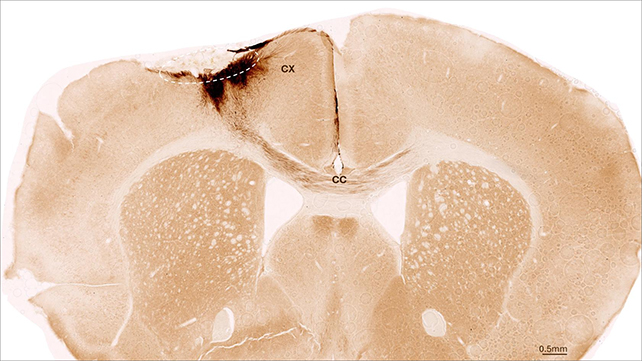

Mouse brain cross section.Image of a mouse brain showing the stroke area (dashed circle) and the projections of the transplanted human stem cells (dark brown). (UZH)

Using mice with stroke-induced brain damage, the researchers found that injections of human stem cells could successfully develop into immature brain cells. The results were dramatic: most of the implanted cells remained in place, developing features of fully functioning neurons and communicating with surrounding cells.

What’s more, the researchers observed blood vessels self-repairing, inflammation in the brain reducing, and the blood-brain barrier growing stronger. The mice even showed signs of improved movement and coordination – a key finding, as strokes can seriously impair the body’s motor control.